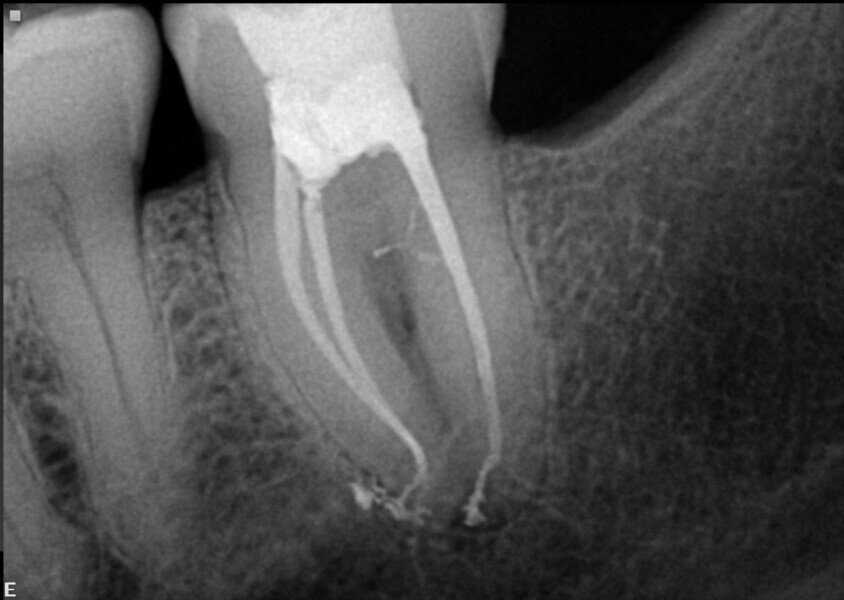

With this software, a 3D model of the tooth with the canals traced with their approximate working lengths can be visualised, giving us an idea of what to expect (Fig. 4). For example, in this case, the average working length was around 27 mm for this second maxillary molar with four canals and this kind of anatomy—I call these cases a double espresso because they are a bit of a challenge. For example, the distal canal had a sharp curve like a hook at the apex. All this data can help in choosing a file sequence for the shaping and cleaning of the root canal system. Traverse and ZenFlex files (Kerr Dental; Fig. 5) were used to shape the canals. In the distal root, the 30/.04 file was not used in the last 2 mm, in order to avoid any misshaping of this area. The irrigation was performed according to the Sleiman sequence of irrigation (published in roots magazine 1/2014). 3D obturation of the canals was performed with the elements IC obturation system (Kerr Dental; Fig. 6). Obturation was completed, and the immediate postoperative radiographs showed that all the canals were filled and sealed (Figs. 7a–c).